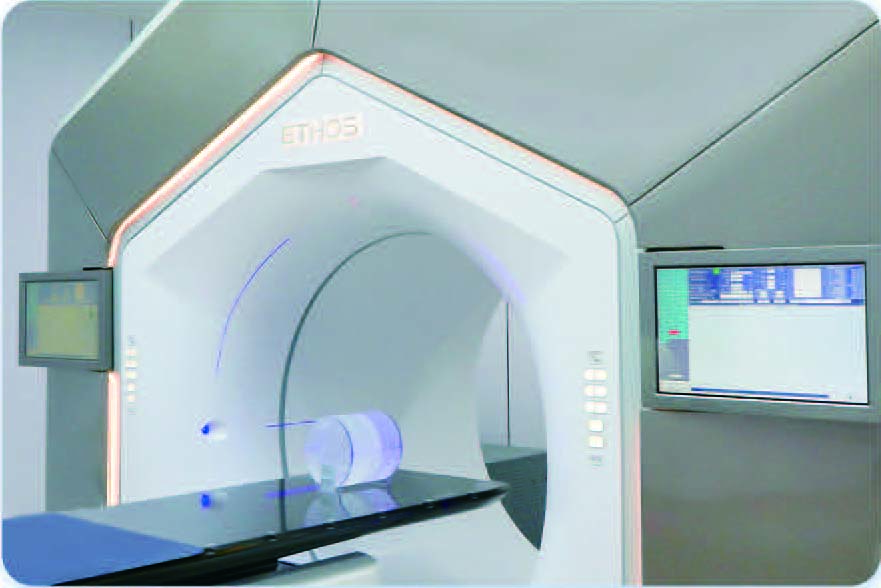

Ethos Intelligent Radiotherapy Platform Pioneering a New Era of Individualized Intelligent Radiation Therapy

Al-driven Adaptive Radiotherapy Platform

What is the Ethos Linear Accelerator?

The Ethos system imported by our hospital is the world’s first online adaptive radiotherapy system based on artificial intelligence technology. It builds upon conventional linear accelerators by incorporating cutting-edge technologies such as artificial intelligence, multimodal high-definition imaging, efficient imaging scanning, and online quality control systems, enabling efficient online adaptive radiotherapy.

The online adaptive radiotherapy of Ethos obtains the patient’s current position image before treatment every day, uses artificial intelligence to adjust the target area and modify the plan in real time, so that every time the patient is treated, the radiation can be accurately projected to the tumor area, achieving accurate individualized radiotherapy every time. It has obvious advantages, especially in prostate cancer, bladder cancer, cervical cancer, endometrioma, rectal cancer and other tumors in parts that change greatly with the filling degree of the intestine and bladder.